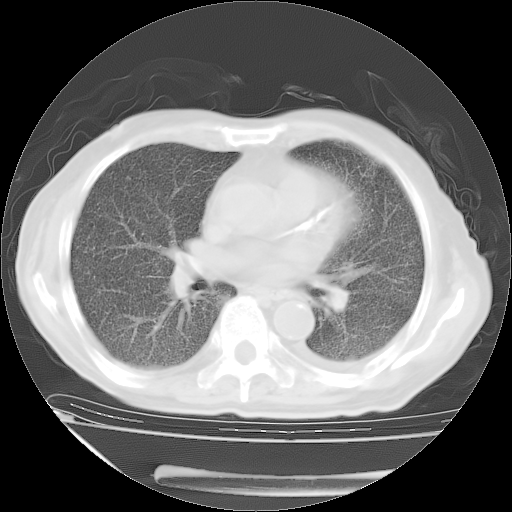

经过24天治疗,岳父的病情基本稳定。生活基本可以自理,可以下床活动。呼吸困难早已消失。体温基本正常。

只是甲强龙用80mg时血小板升到正常,改为60mg后又降到63×10*9/L。

主要治疗甲强龙80mg×14天,60mg×10天;同时抗结核(异烟肼+利福平+乙胺丁醇)。环磷酰胺0.1 tid 10天。

特别感谢胡教授、高管、桃子版主给出关键的治疗建议。桃版把所有肺部影像和全部临床资料请所在医院呼吸科、感染病科、结核科、临床免疫科专家会诊。临床免疫科专家制定了完整的治疗方案。